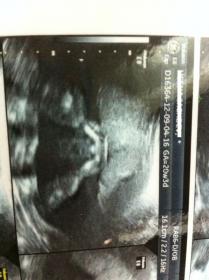

this is at 20 weeks...

Pls guess whether its boy or girl ? Very Confused

Is that a potty shot? If all the bits are what I think they are, I'm going with boy. :)

Boy

Yep a boy :) congrats

thanx a lot for ur wishes....i so want a boy....i wish u all r right...will update u all once i find d gender...